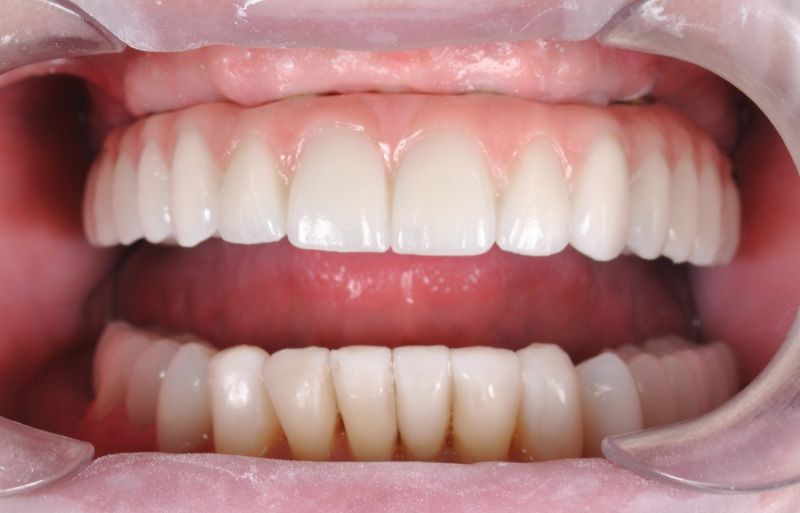

Wykonana praca protetyczna:

- most pełnołukowy na sześciu implantach

- korony na zęby własne w łuku dolnym

- korony na implantach w miejscach braków zębów

- odbudowa flow-injection zębów dolnych przednich

Praca wykonana przez: dr n. med. Michała Kubiszyna

Leczenie zachowawcze i endodontyczne: lek. dent. Paweł Kruk

Leczenie periodontologiczne: hig Emilia Łosicka